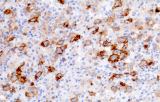

- Linfoma di Hodgkin classico: le cellule tumorali sono tipicamente CD30+ e spesso CD15+, con PAX5 debole e CD20 negativo nelle grandi cellule tumorali.